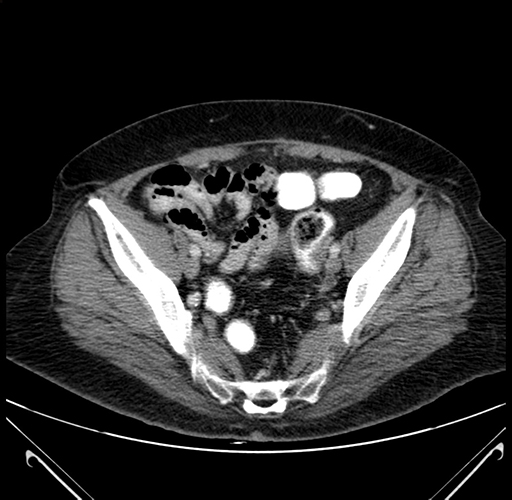

Axial Venous

Coronal Venous